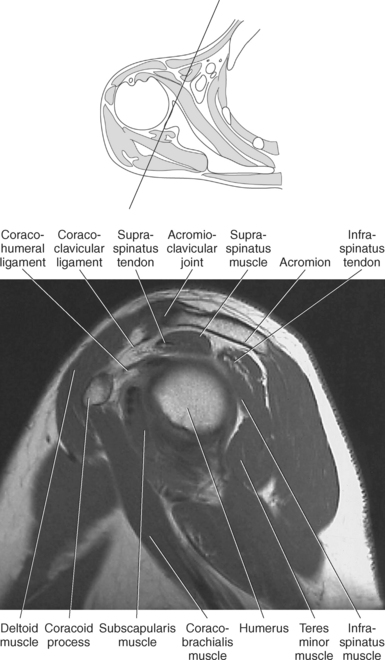

The edge of the glenoid fossa is surrounded by a fibrocartilaginous ring termed the glenoid labrum (glenoid lip) (Figure 9.17). The glenoid labrum is a fold of the articular capsule, which functions to deepen the articular surface of the glenoid fossa. Superiorly, the labrum blends with the long head of the biceps brachii muscle. In cross section it appears triangular (Figure 9.18). The three glenohumeral ligaments (superior middle, and inferior) are thickenings of the fibrous capsule that surrounds the shoulder joint; they contributes to the formation of the glenoid labrum (Figures 9.17 and 9.19). They extend from the supraglenoid tubercle of the scapula to the lesser tubercle of the humerus. Also aiding in strengthening the fibrous capsule is the coracohumeral ligament that passes from the lateral side of the coracoid process of the scapula to the anatomic neck of the humerus (Figure 9.19). The coracoacromial ligament is another important ligament located on the anterior portion of the shoulder. As this ligament joins the coracoid process and acromion, it forms a strong bridge, termed the coracoacromial arch, which protects the humeral head and rotator cuff tendons from direct trauma and prevents displacement of the humeral head superiorly (Figures 9.17 and 9.19). The coracoclavicular ligaments help to maintain the position of the clavicle, in relation to the acromion, by spanning the distance between the clavicle and coracoid process of the scapula (Figure 9.19). The acromioclavicular ligament, at the acromioclavicular joint, provides support for the superior surface of the shoulder (Figures 9.17 and 9.19). The transverse humeral ligament is a broad band of connective tissue passing from the greater tubercle to the lesser tubercle of the humerus, forming a bridge over the intertubercular groove for protection of the long head of the biceps tendon (Figure 9.19). The ligaments of the shoulder are demonstrated in Figures 9.20 through 9.30.

Figure 9.27 Axial, T1-weighted MR scan of shoulder.

Key: c, Clavicle; cc, coracoclavicular ligament; CP, coracoid process; ch, coracohumeral ligament; D, deltoid muscle; H, humeral head; SB, subscapularis muscle; SS, supraspinatus muscle; G, glenoid fossa; L, labrum; ss, supraspinatus tendon; b, tendon of long head of biceps muscle; IG, inferior glenohumeral ligament; mg, middle glenohumeral ligament; sb, subscapularis tendon; T, teres minor muscle.